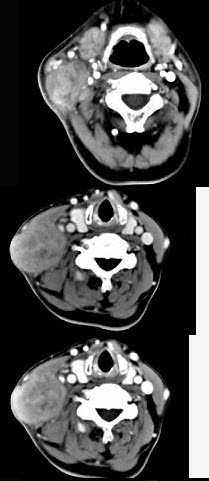

- 单项选择题65岁男性,吸烟史30余年,近半年来颈部出现疼痛性肿块,CT扫描如图所示,请选择最可能诊断()。

- D